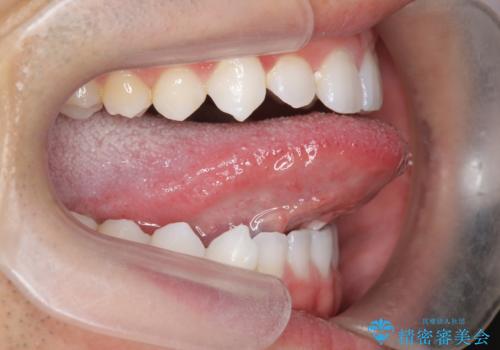

切除後、しっかり上にもつくようになり、前にも大きく出せるようになりました。